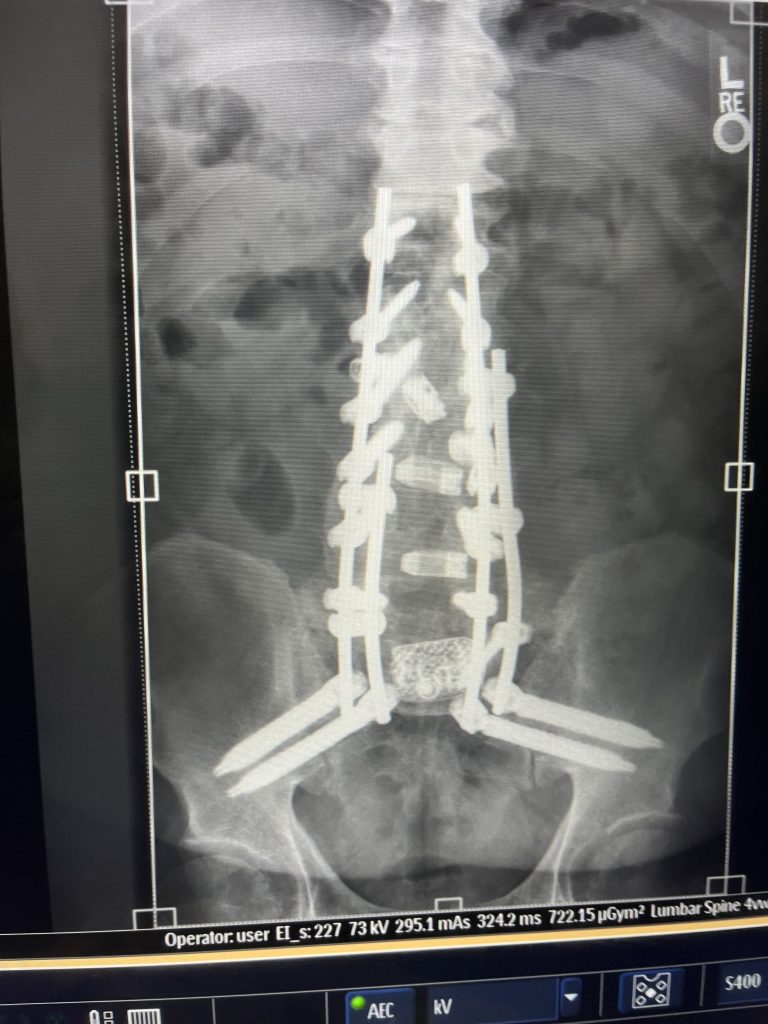

Dr. Qureshi performed a flawless minimally invasive procedure to fuse five vertebrae. Unfortunately, through no fault of his own, my body did not allow the fusion to heal properly after a year. When I returned to him, he immediately connected me with another outstanding surgeon - Dr. Francis Lovecchio - and arranged for me to meet him that same day.

Dr. Lovecchio was compassionate and reassuring, promising to walk with me through every step of this process. He later performed two extensive spinal surgeries that freed up the nerves in my left leg and foot - areas where I previously had no feeling at all. Today, I can feel my leg and foot again, something I thought I had lost forever.